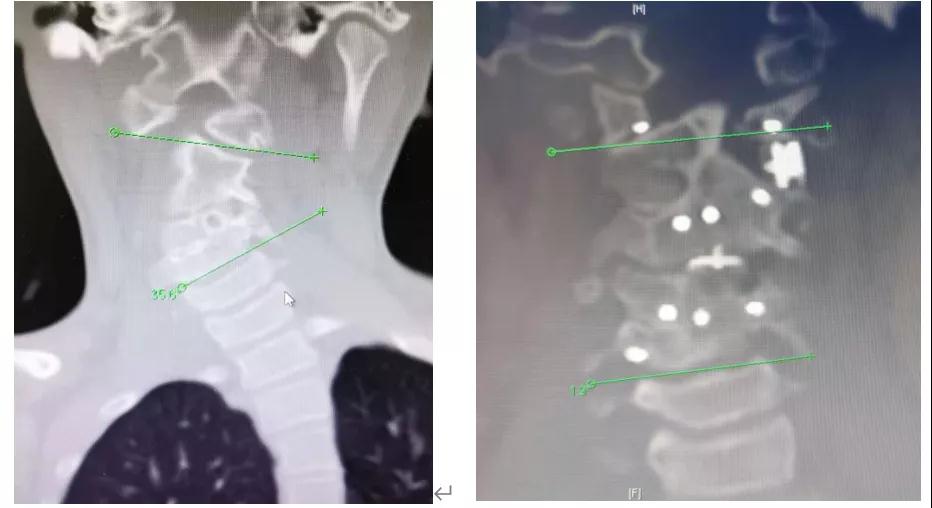

小女孩入院之后,孙宇专家团队对该小女孩的病情进行了术前讨论。术前CT报告:C2-5阻滞椎、发育畸形,寰枢椎脱位,C4椎体囊样骨质缺损。该患者术前诊断为:脊柱侧弯、斜颈、椎体分隔不全(C2-3,C4-5),椎弓根分隔不全(C3-4)。孙宇主任的专家团队对于治疗骨性斜颈有着自己的独特的理念:“削峰、填谷”,即通过去除骨性斜颈患者颈椎椎体侧凸一侧的多余骨质,填补凹陷一侧椎体所缺少的骨质,使得侧弯颈椎两侧达到应力平衡,从而矫正颈椎畸形。考虑侧弯C1-2和C3-4的韧带及软组织挛缩、骨质缺失,而右侧C4-5椎体间骨质融合,因此决定行颈前路C3-4椎间盘切除,双侧钩椎关节及韧带松解术,颈后路C1-2和C3-4左侧小关节切除及韧带松解,C4-5右侧椎板间截骨,左侧C1、C2、C4和右侧C1、C2、C5椎弓根螺钉内固定术。同时,采用本院的领先国际的3D打印技术,行C1-2(左侧)和C3-4(左侧)关节突3D打印椎间融合器植入植骨融合,颈前路C3-4椎间隙3D打印椎间植入植骨融合术。

小女孩收入院后,经过评估可以耐受手术。经过几天术前复合牵引,寰枢椎和颈3-4左侧塌陷的颈椎间隙被部分牵开,斜颈获得部分矫正。充分的术前准备后,2021年2月2日上午9:00,手术如期开展。整个手术过程非常顺利,由于患者病情复杂,手术耗时接近10个小时,但是在孙宇主任及颈椎组其他专家的精细的操作下,手术有条不紊地进行。最终,将原本塌陷的寰枢椎和颈3-4左侧的椎间隙分别撑开9mm。斜颈矫正率大约95%。当日晚上19:00,手术顺利结束。手术当中,1:1尺寸3D打印骨骼模型、3D高清脊柱外科专用手术显微镜、电子计算机辅助术中导航、精细超声骨刀、电子束熔融3D打印定制融合器、1毫米精细刮匙和咬骨钳等高新科技设备和器械发挥了重要作用。

手术前后CT对比照片